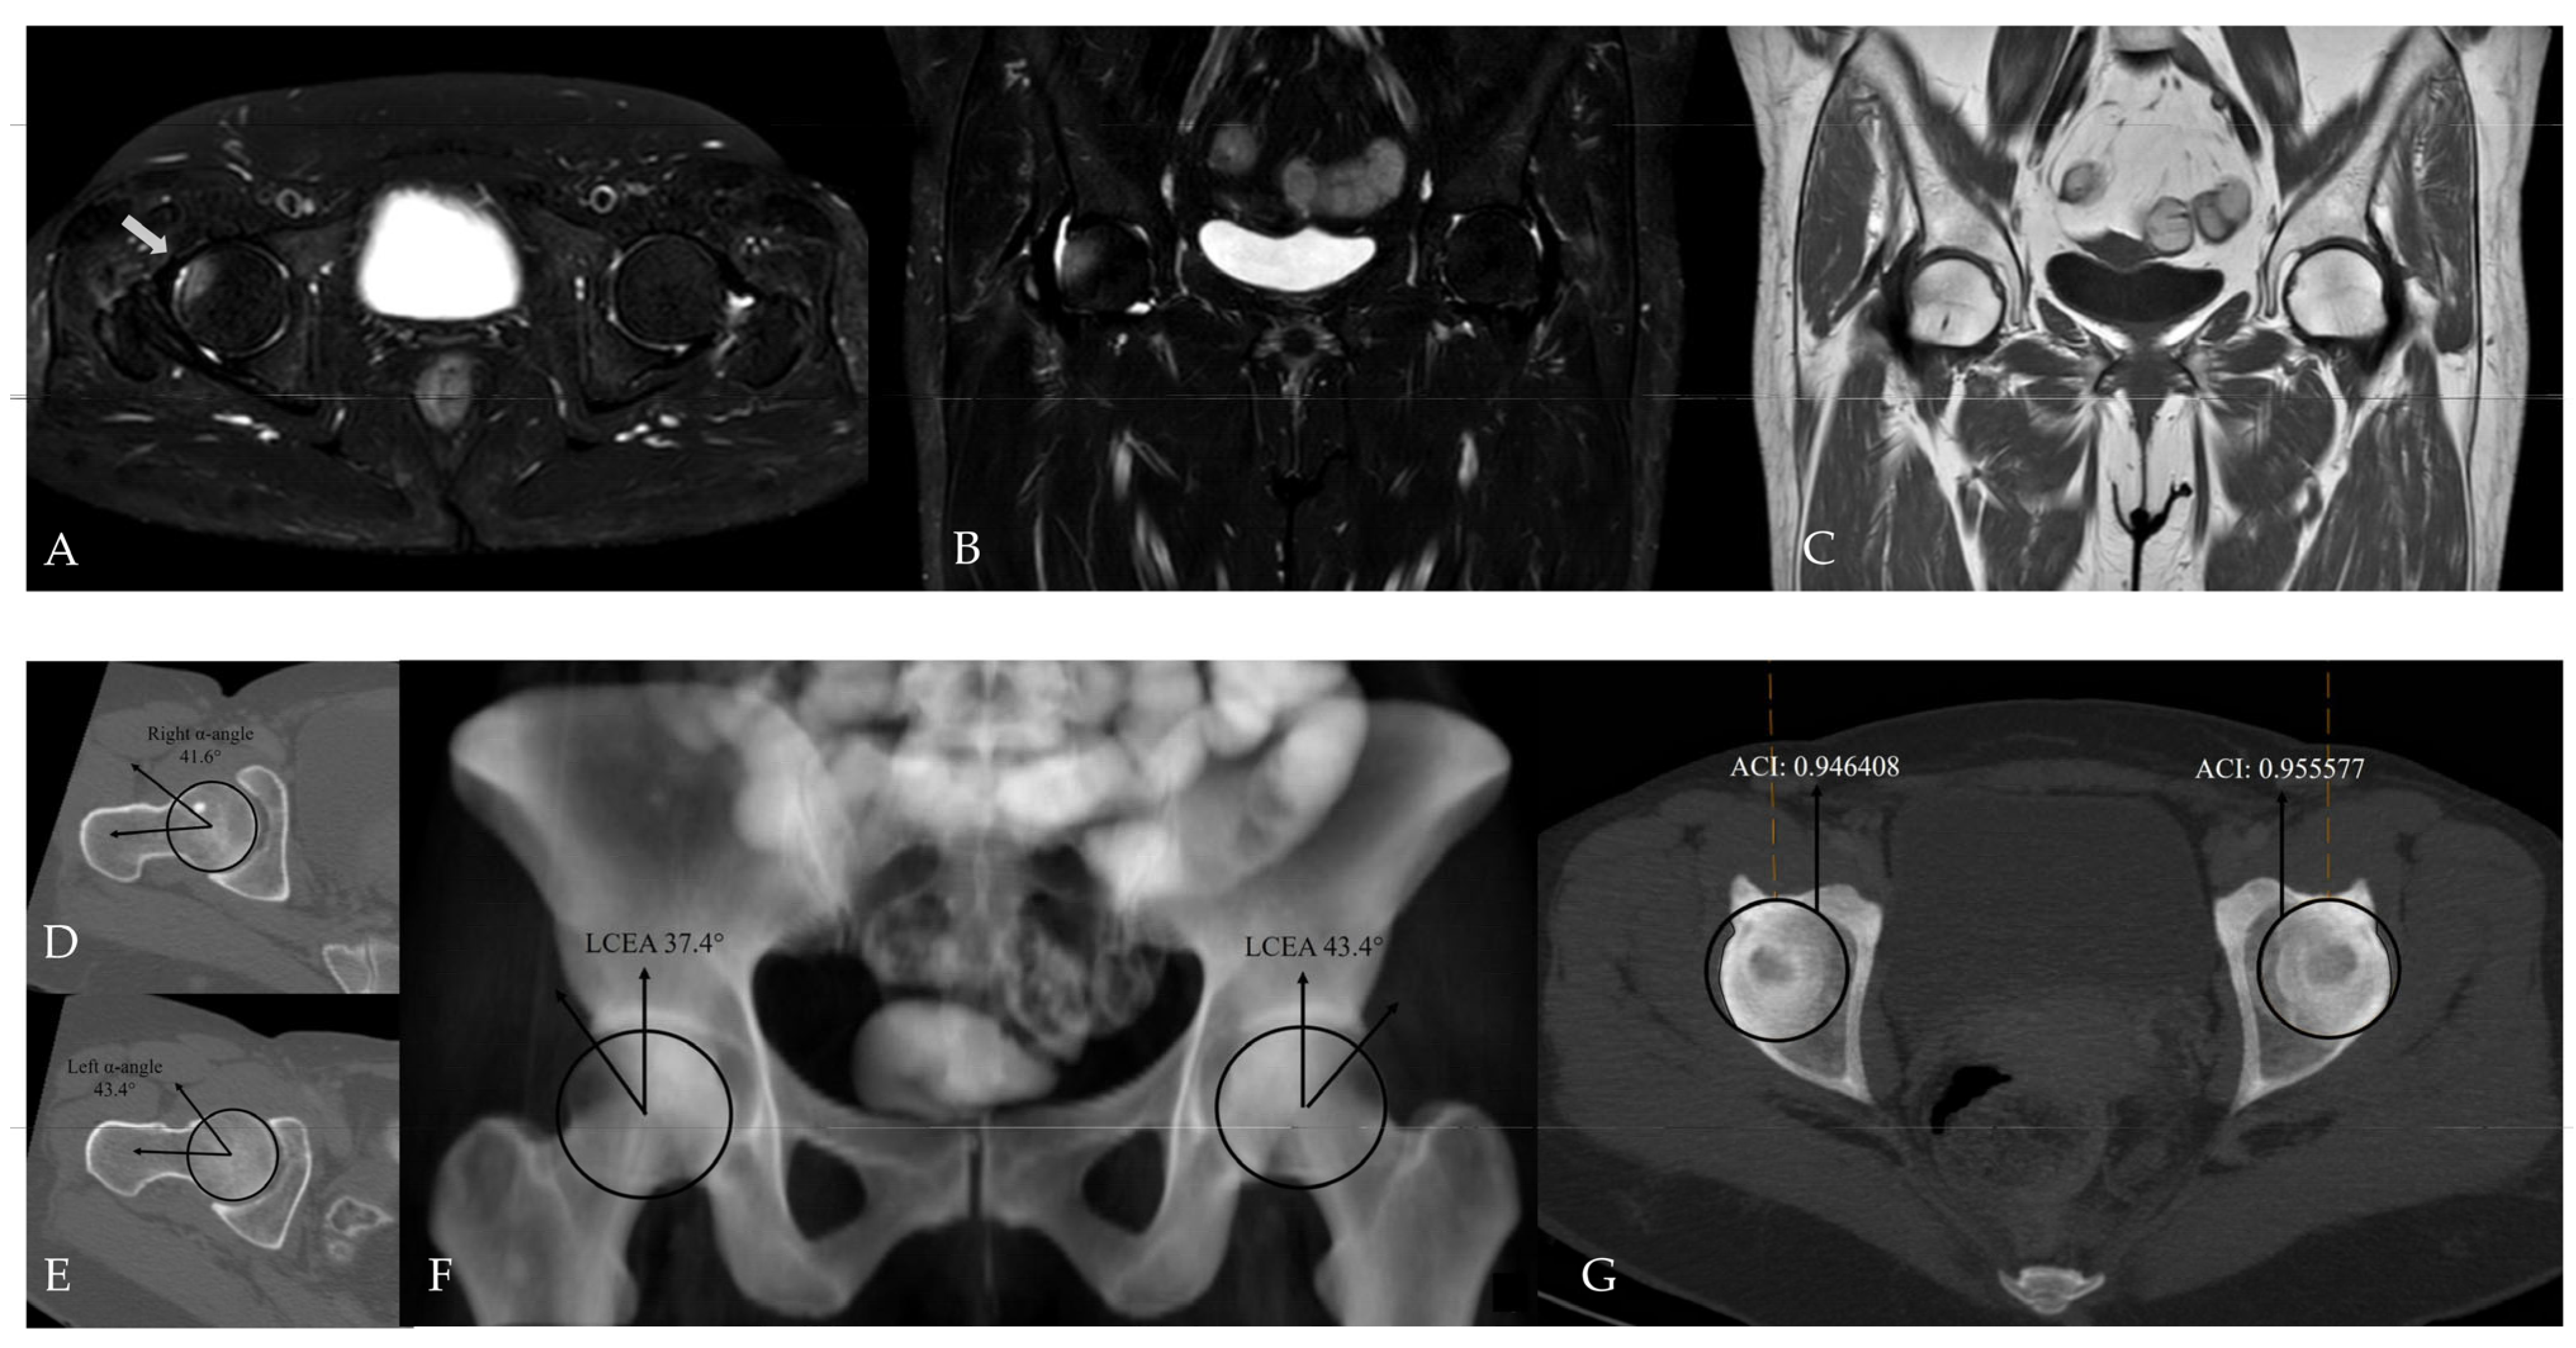

Figure 7.

Hip MRI demonstrates focal bone marrow edema in the anterolateral aspect of the right femoral head on (A) axial (white arrow) and (B) coronal fat-suppressed T2-weighted images. (C) Coronal T1-weighted image shows no underlying structural abnormality. (D,E) CT demonstrates normal alpha angle measurements. (F) LCEA measurements indicate pincer-type femoroacetabular impingement only on the left side. (G) However, using an ACI cut-off value of 0.93, bilateral pincer-type femoroacetabular impingement can be demonstrated.

Figure 8.

Hip MRI demonstrates bilateral posterolateral femoral head bone marrow edema on (A) axial (white arrows) and (B) coronal fat-suppressed T2-weighted images, more pronounced on the right, with associated right hip joint effusion. (C) Coronal T1-weighted image shows no structural abnormality. (D,E) CT shows normal alpha angle measurements, and (F) LCEA values are within normal limits. (G) However, the ACI exceeds the 0.93 cut-off value on the left, while CT–MIP images demonstrate posterior acetabular rim overcoverage on the right without marked posterior wall lateralization.

Figure 9.

Hip MRI demonstrates focal bone marrow edema in the inferior aspect of the left femoral head on (A) axial and (B) coronal fat-suppressed T2-weighted images (white arrow). (C) Coronal T1-weighted image shows no associated additional imaging findings. (D,E) CT demonstrates alpha angle measurements, and (F) LCEA measurements indicate bilateral mixed-type femoroacetabular impingement. (G) Acetabular overcoverage is confirmed using the ACI.